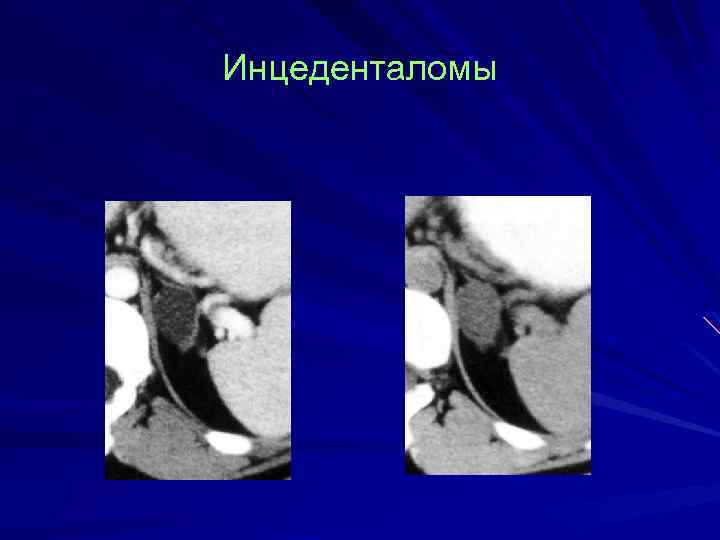

Инцеденталомы